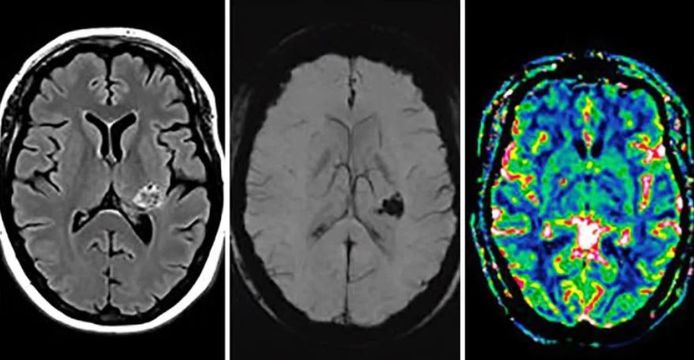

De hersenen het ruggenmerg en de zenuwen vormen samen het zenuwstelsel. AMSTERDAM - Een hersentumor verstoort niet alleen hersenfuncties in zijn directe omgeving maar ook. Een neuraal netwerk is zowel in opbouw als in werking een imitatie van onze eigen hersenen.